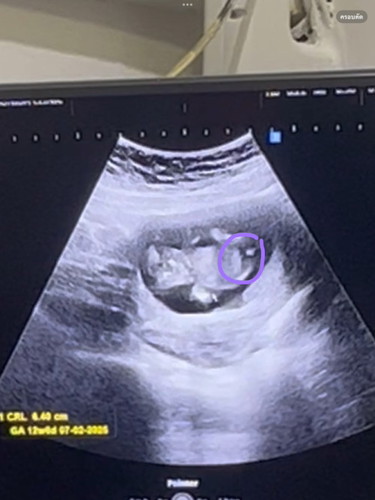

ไปซาวด์มาดูหมอว่ายังเห็นไม่ชัด แต่แม่เหมือนเห็นเพศชาย ใช่มั้ยคะ

กำลังตั้งครรภ์